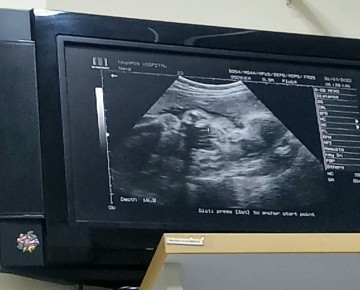

บ้านนี้หมอกำหนดคลอด 12ตุลา จะลาคลอดช่วงไหนดีค่ะแม่ๆ บางคนบอกกลางเดือนกันยา บางคนบอกสิ้นเดือนกันยา พอดีจะกลับไปคลอดที่บ้านต่างจังหวัด ขอคำแนะนำจากแม่ๆหน่อยค่ะ🥰😊